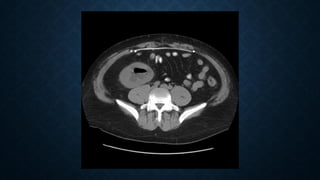

• C+ portal venous phase

• Acute Pyelonephritis 1; seen as focal lower pole low attenuation